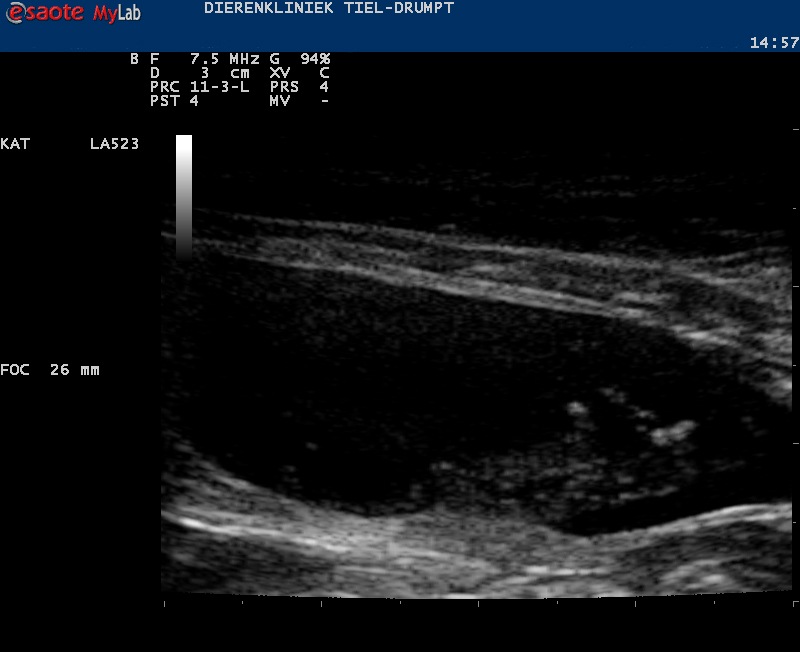

Zo kan er sprake zijn van zwelling of een gezwel bij de penis of een verstopping in de plasbuis door bijvoorbeeld samengeklonterd gruis, een blaassteentje of een plug (dit wordt gevormd door eiwitten, cellen, etc) die een verstopping kunnen geven.Ook structuren in de blaas kunnen de uitmonding verstoppen, zoals steentjes, poliepen, gezwellen, etc.

Het eerste dat moet gebeuren bij de behandeling is zorgen dat de urine uit de blaas kan, zodat de kat zijn gifstoffen kwijt kan. Hierbij, of direct hierna proberen we de oorzaak vast te stellen. Dit om te voorkomen dat er lang behandeld wordt zonder een goede kans op genezing.

De kater wordt in slaap gebracht, waarna er geprobeerd wordt om de plasbuis in de penis vrij te krijgen. In de meeste gevallen gaat het om een ontstekingsplug of gruis en in deze gevallen zal er een urinekatheter ingebracht worden. Deze wordt vastgehecht en moet een aantal dagen blijven zitten. De katheter zorgt voor een continue mogelijkheid tot het afvoeren van de urine, waarbij tevens de blaaswand rust krijgt. Na een aantal dagen spoelen en behandelen met medicatie halen we de urinekatheter eruit en zal er gecontroleerd moeten worden of de klachten niet terugkomen.